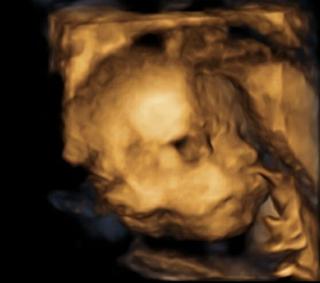

Tak teď už v úterý na 4D ultrazvuk a pak hned na předporodní kurz s tatínkem 🙂

Na 4D jdeme taky, už se mooc těším!!! je to nádhera!! zrovna dneska jsem se koukala video s Helí.

@favofrenki jé paráda:D moc hezký fotky! Já na tomhle ultrazvuku byla už hodněkrát(moje mamka je točí) a pokaždý si to skvěle užívám🙂